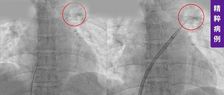

阜外医院宋雷、崔成教授高血栓负荷编织样血管PCI治疗一例

阜外医院宋雷、张茵教授-LAD-CTO PCI开通一例